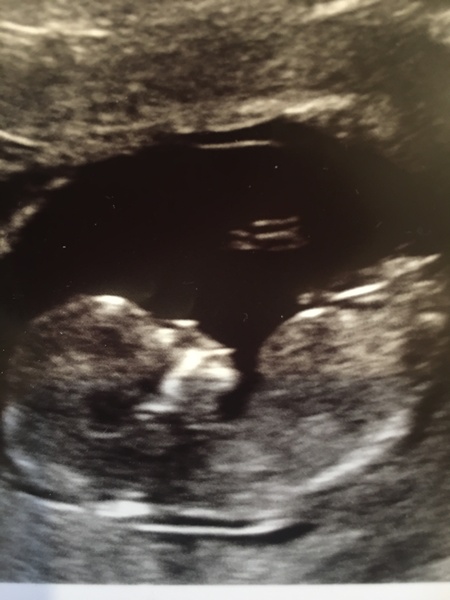

Bikbikmum · 27/12/2019 19:47

This is our last week scan , 13+ 4 today. My due date is 29.06 now . Can't wait till another scan in February!

Due end of June/start of July 2020